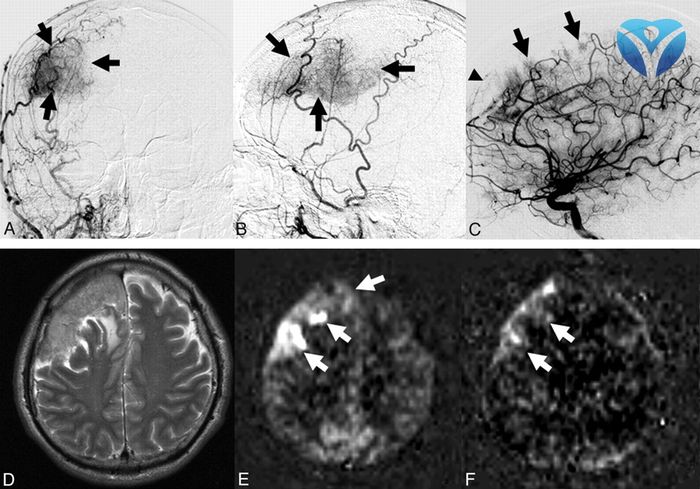

Так было и в случае запорожанки Валентины Григорьевны. У пациентки диагностировали опухоль головного мозга. И хоть из всех новообразований опухоли мозга занимают лишь 2%, часто этот диагноз равносилен смертельному приговору. Женщина до последнего надеялась, что ее проблемы со здоровьем временны, но нужна была операция на головном мозге. Используя возможности нового ангиографа Toshiba, нейрохирурги ЗОКБ провели первый этап операции по «отключению» питания опухоли от кровотока, снизив риски внутричерепного кровотечения, а затем «на сухую» провели удаление опухоли, тем самым спасли жизнь женщины. Такие операции действительно уникальны для Запорожского региона и выполняются только в Запорожской облбольнице при помощи ангиографа Toshiba.

Опухоль головного мозга через призму ангиографа